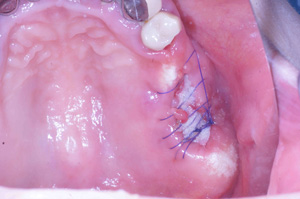

@@R.S‚³‚ñ@56Î —«  ‘åŠw‹³Žö @Žèp“ú@‚Q‚O‚O‚W”N ‚QŒŽ ‚X“úi“yj@㉺Š{  ƒm[ƒxƒ‹ƒKƒCƒhŽg—p@Ö¬“à’ÁÖ@•¹—p@@@

@@@@@ãŠ{  All on ‚U@‘¦Žž‰Ád@@

@@@@@@@@@@@@@ Rpl Tapered Rp  ‚P‚O mm(‚U–{)

@@@@@‰ºŠ{¶‰E@‘¦Žž‰Ád@ ‚R Unit Bridge@

@@@@@@@@@@@ @Rpl Tapered Rp  ‚P‚O mm(‚S–{)@@–ƒWƒ‹ƒRƒjƒAƒNƒ‰ƒEƒ“‚ÅÅI•â’Ô